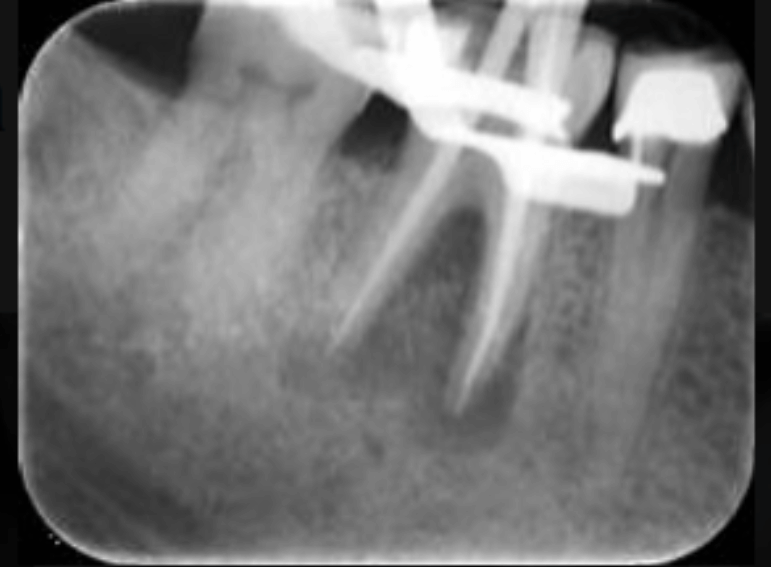

Case 4 – Endodontics

Single visit root filling of a molar and core.